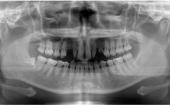

パノラマ撮影法パノラマレントゲンは、上下全ての歯・骨の状態などが、一枚のレントゲンで撮影できます。 |